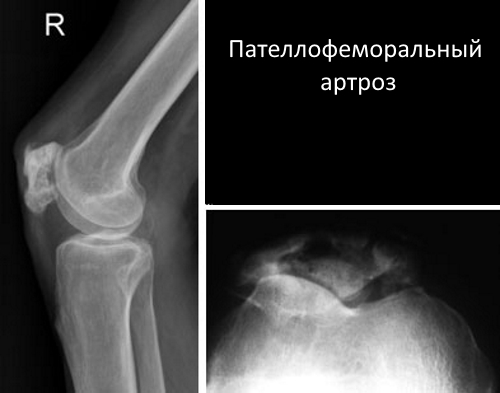

Основная классификация пателлофеморального артроза основана на степени повреждения суставных элементов:

- При первой степени рентгенография не показывает признаков нарушения целостности хрящевых поверхностей. В это время уже наблюдается воспалительный процесс с легкими симптомами.

- На второй степени рентгенография выявляет признаки прогрессирующего дегенеративно-дистрофического процесса, затрагивающего значительные участки хрящевой ткани. Симптомы становятся более выраженными.

- При третьей степени на рентгеновских снимках видны значительные дегенеративно-дистрофические изменения хрящевых поверхностей надколенника и бедренной кости. Также наблюдаются явные признаки поражения головки кости. На этой стадии заболевание сопровождается выраженной симптоматикой и ограничением подвижности сустава.